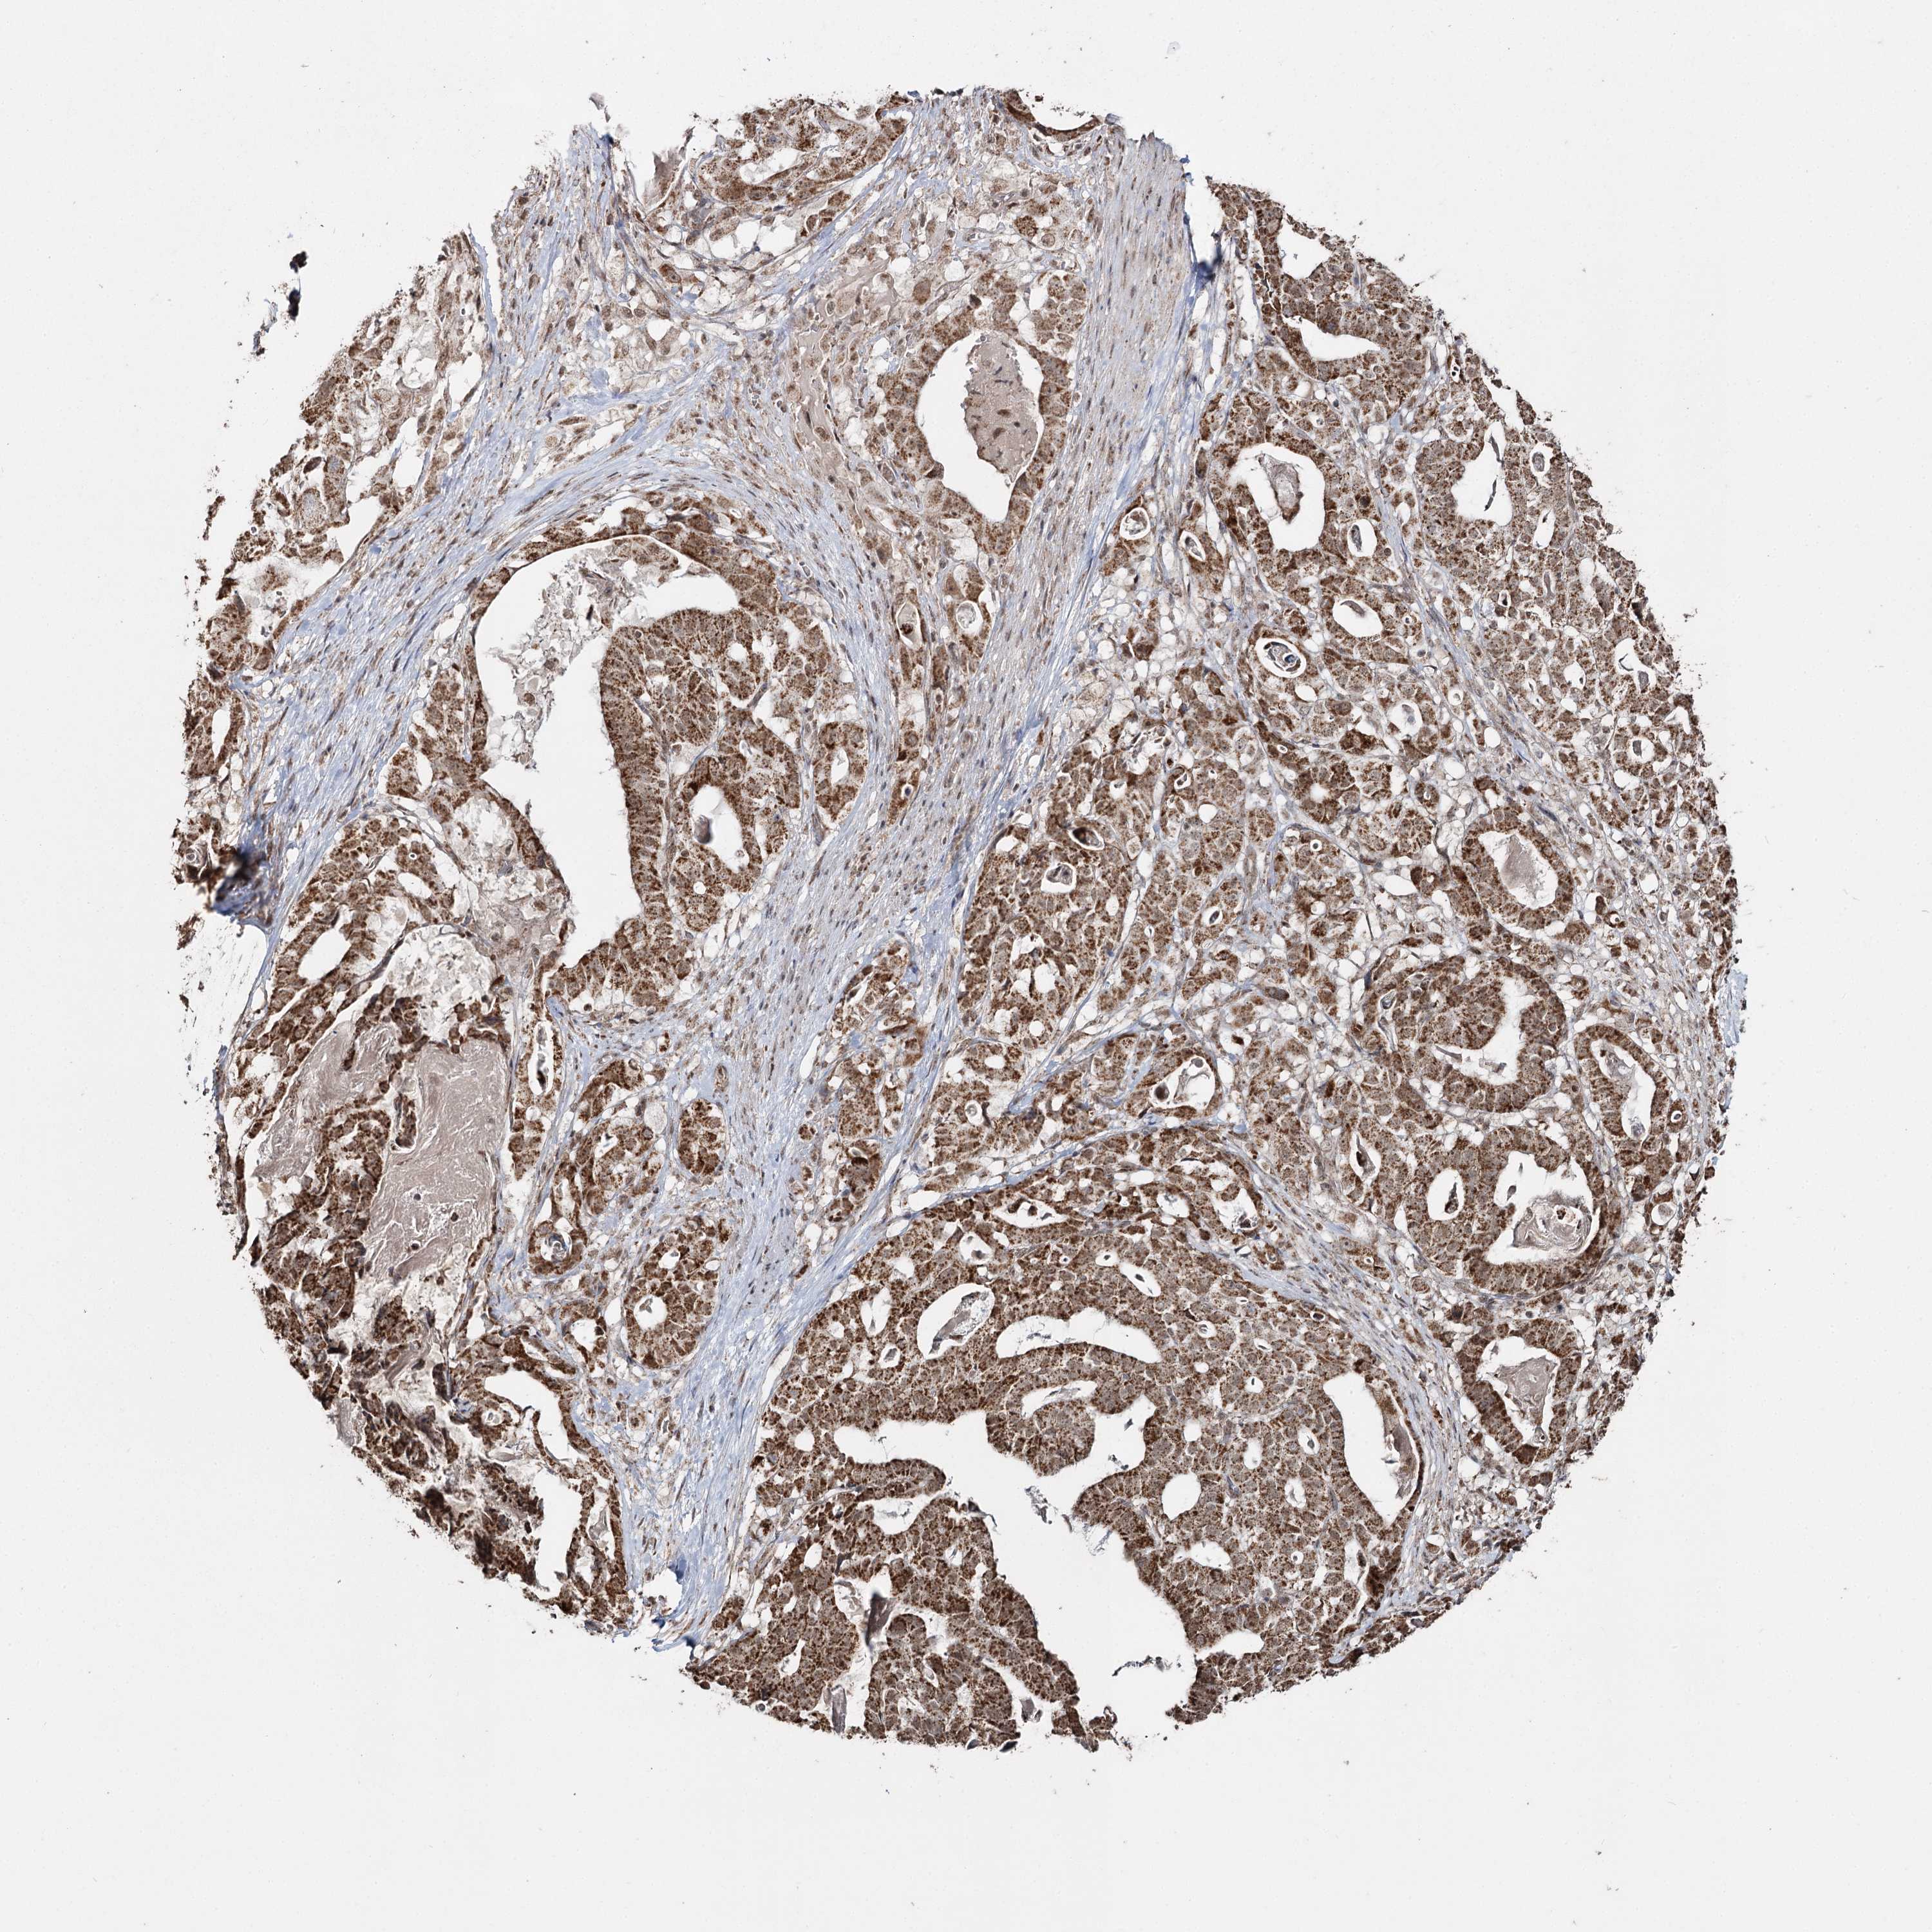

STOMACH CANCER - Protein expressioni

A mouse-over function shows sample information and annotation data. Click on an image to view it in a full screen mode. Samples can be filtered based on level of antibody staining by selecting one or several of the following categories: high, medium, low and not detected. The assay and annotation is described here.

Note that samples used for immunohistochemistry by the Human Protein Atlas do not correspond to samples in the TCGA dataset.

Antibody stainingi

Antibody staining in the annotated cell types in the current human tissue is reported as not detected, low, medium, or high, based on conventional immunohistochemistry profiling in selected tissues. This score is based on the combination of the staining intensity and fraction of stained cells.

Each image is clickable and will lead to virtual microscopy that enables deeper exploration of all samples and also displays staining intensity scores, fraction scores and subcellular localization as well as patient and tissue information for each sample.

Antibody HPA038484

Antibody HPA038485

Staining

High

Medium

Low

Not detected

Intensity

Strong

Moderate

Weak

Negative

Quantity

>75%

75%-25%

<25%

None

Location

Nuclear

Cytoplasmic/membranous

Cytoplasmic/membranous,nuclear

Adenocarcinoma, NOS

Adenocarcinoma, High grade